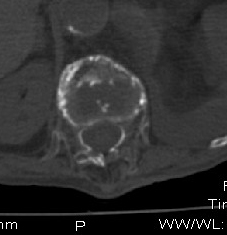

男:89岁因外伤后2天行ct检查。请各位战友讨论图中所指是否是骨折和形成该影像的原因(扫描层面位于椎体中份)。

老年性骨质疏松,椎体前缘出现双边征支持压缩骨折。椎体骨质稀疏,似有破坏,警惕溶骨性骨转移。

椎体前缘双边征,其后椎体内密度增高均提示压缩性骨折

压缩性骨折,骨质疏松,前缘密度增高,考虑压缩所致

椎体前缘呈双边征 考虑 压缩性骨折,椎体退行性病变。

我的报告1:腰椎骨质退行性改变。

2:t12改变考虑压缩骨折?请结合临床。

骨质疏松,考虑陈旧压缩性骨折.(有硬化边).